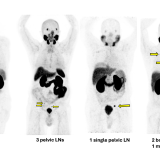

figure of PSMA PET scans

Cancer,

Science & Research

New therapy delays progression of recurrent prostate cancer

Patients with recurring prostate cancer who were treated with a new PSMA-targeted radioligand therapy before stereotactic body radiotherapy went more than twice as long without their disease worsening compared with those who received SBRT alone.